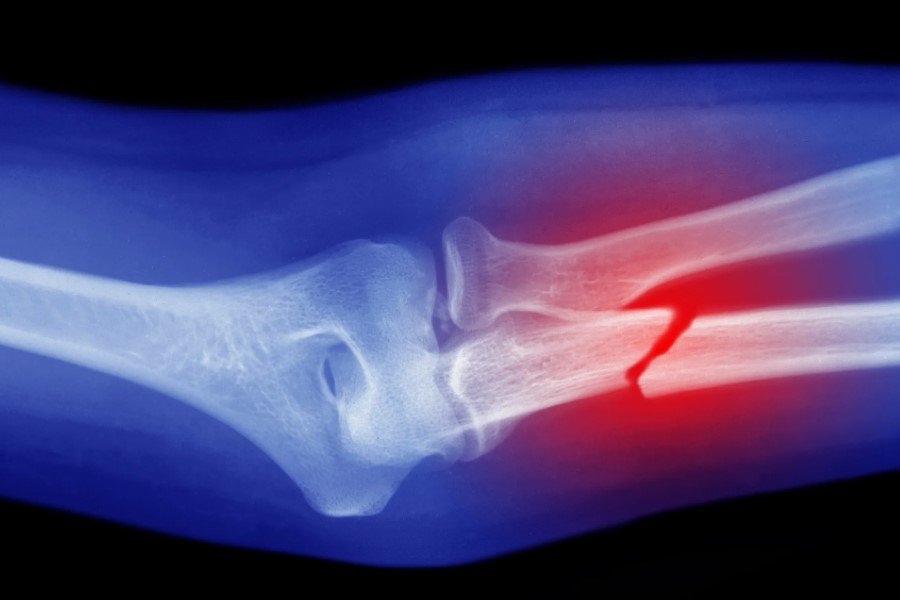

Диагностика переломов

Пойдешь к доктору — он первым делом начнет рассматривать всякие рентгены и томографии. Они круто показывают, что там внутри. Иногда видно даже больше, чем хочется. Без этого никак — знаешь ли, в гипс нужно что-то заворачивать с умом.